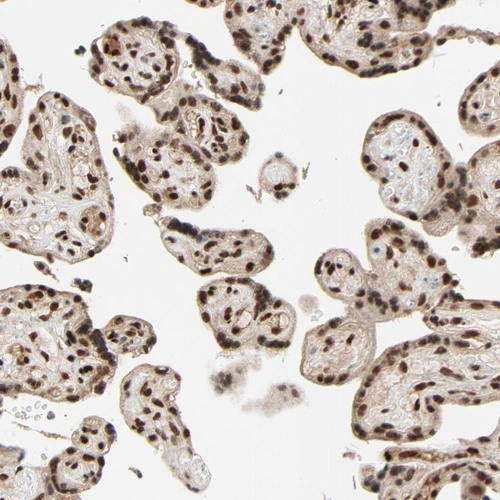

Immunohistochemical staining of human placenta shows strong nuclear positivity in trophoblastic cells.